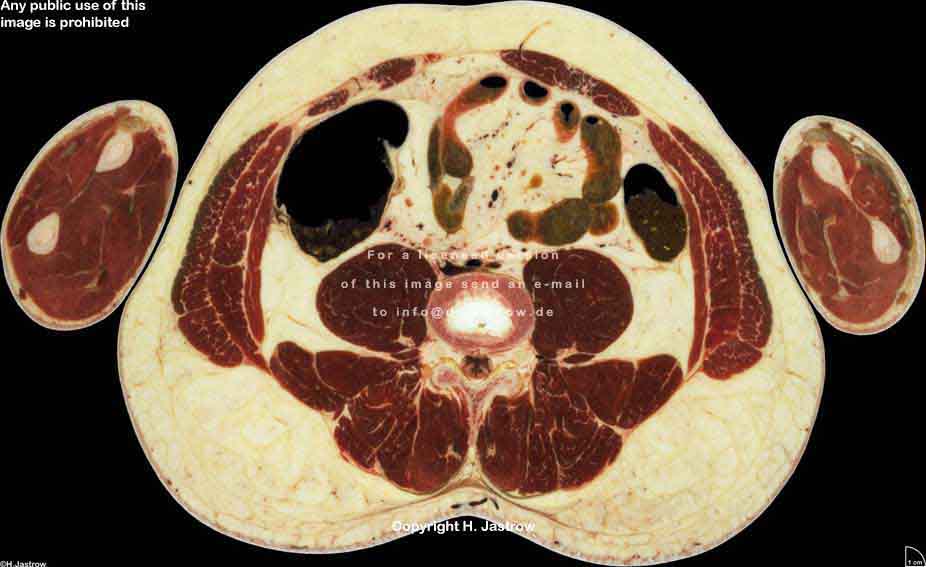

Visible Human male: Sectio transversalis 1723

CT

NMR

Pd                          / T2 \                         T1